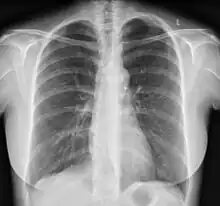

A chest X-ray may be taken, which reveals overall heart size (as a reflection of the combined mass of the cardiac chambers) and the appearance of blood flow to the lungs. A small PDA most often accompanies a normal-sized heart and normal blood flow to the lungs. A large PDA generally accompanies an enlarged cardiac silhouette and increased blood flow to the lungs.